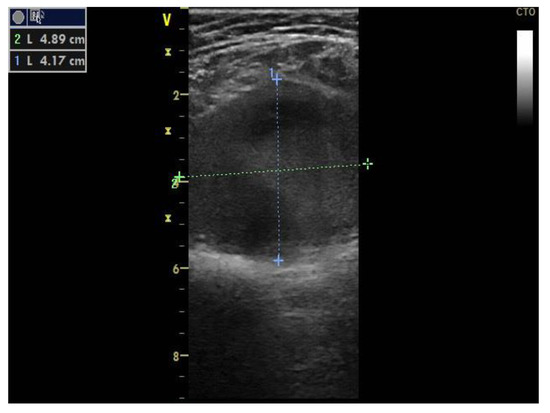

Knee MRI was performed to better describe the extension and anatomy of the aneurysm. It described an aneurysmal dilatation of the distal popliteal vein measuring 64 × 19 × 31 mm, with turbulent blood flow which exerted a mass effect on the adjacent muscle groups (Figure 2).

Figure 2.

Magnetic resonance (MRI) of the knee, longitudinal axis view, showing the anatomy and location of the popliteal vein aneurysm.